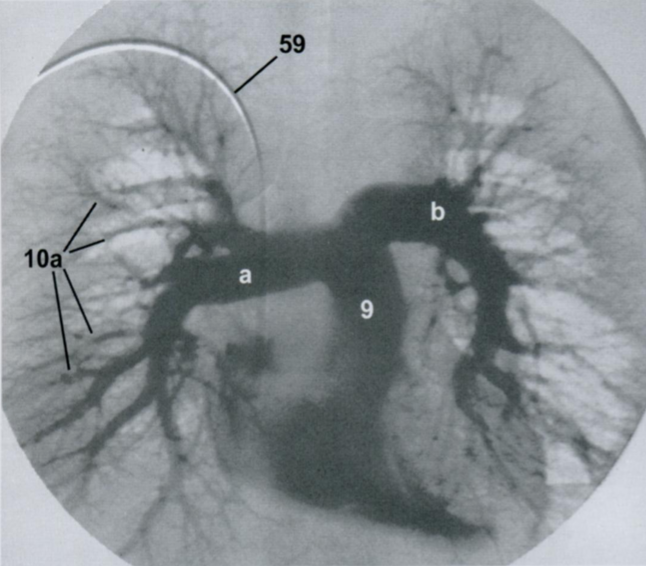

Ангиографическая визуализация сосудов легких.

Какая фаза распространения контраста? Артериальная или венозная?

Назовите все пронумернованные структуры.

Задняя прямая проекция (ЗПП)

Ангиография выполняется с помощью введения контраста через катетер в полой вене, правом предсердии или артериях малого круга.

A

Артериальная фаза. Норма.

9 - легочный ствол

9а - правая легочная артерия

9b - левая легочная артерия

10а - легочные артерии

59 - катетер